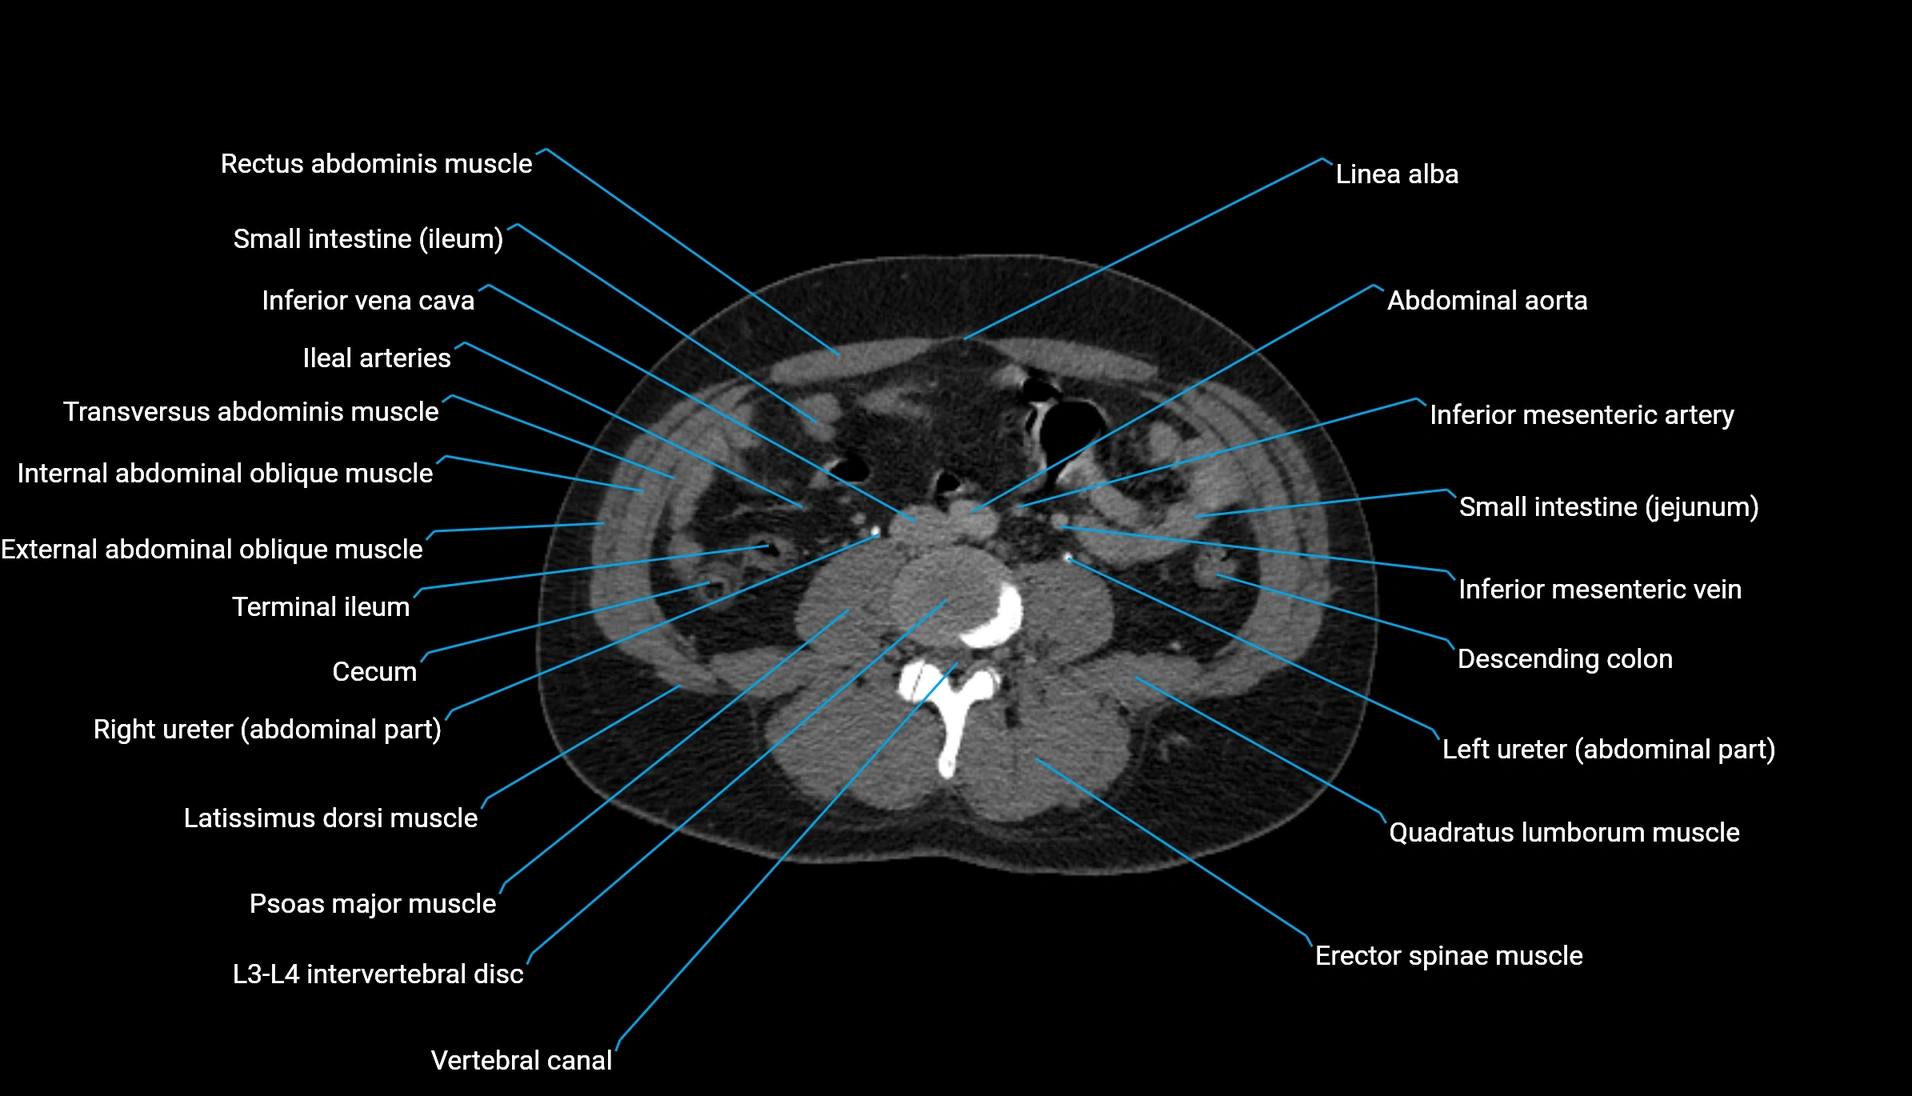

CT Appearance

Non-contrast CT:

-

Demonstrates cortical bone of acetabular rim in excellent detail

Detects fractures, dysplasia, retroversion, or bony overcoverage (pincer impingement)

3D reconstructions used in preoperative hip surgery planning

CT VRT 3D image

CT image